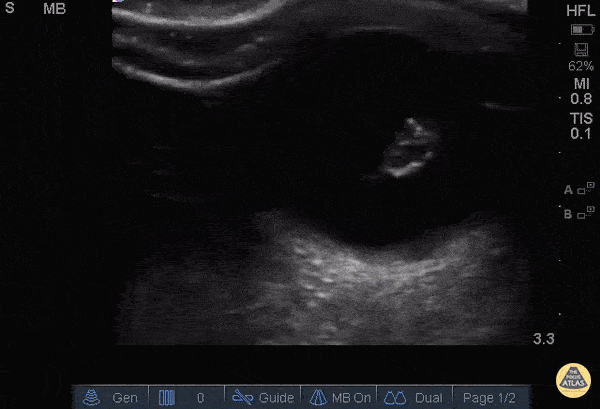

Orbital - Lens Dislocation

Patient with severe maxillofacial trauma of unclear etiology. Ocular POCUS demonstrates a biconvex structure with a hyperechoic rim consistent with traumatic lens dislocation. Dr. Joshua Schechter - SUNY Downstate/Kings County Emergency Medicine